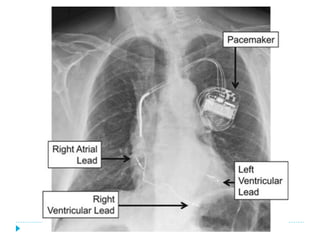

}  Generador de pulso: fuente

de poder o batería.

}  Electrodos o cables.

}  Cátodo (electrodo negativo).

}  Ánodo (electrodo positivo).

}  Tejidos corporales.

IPG

Electrodo

Anodo

Cátodo

Los Componentes del Marcapasos